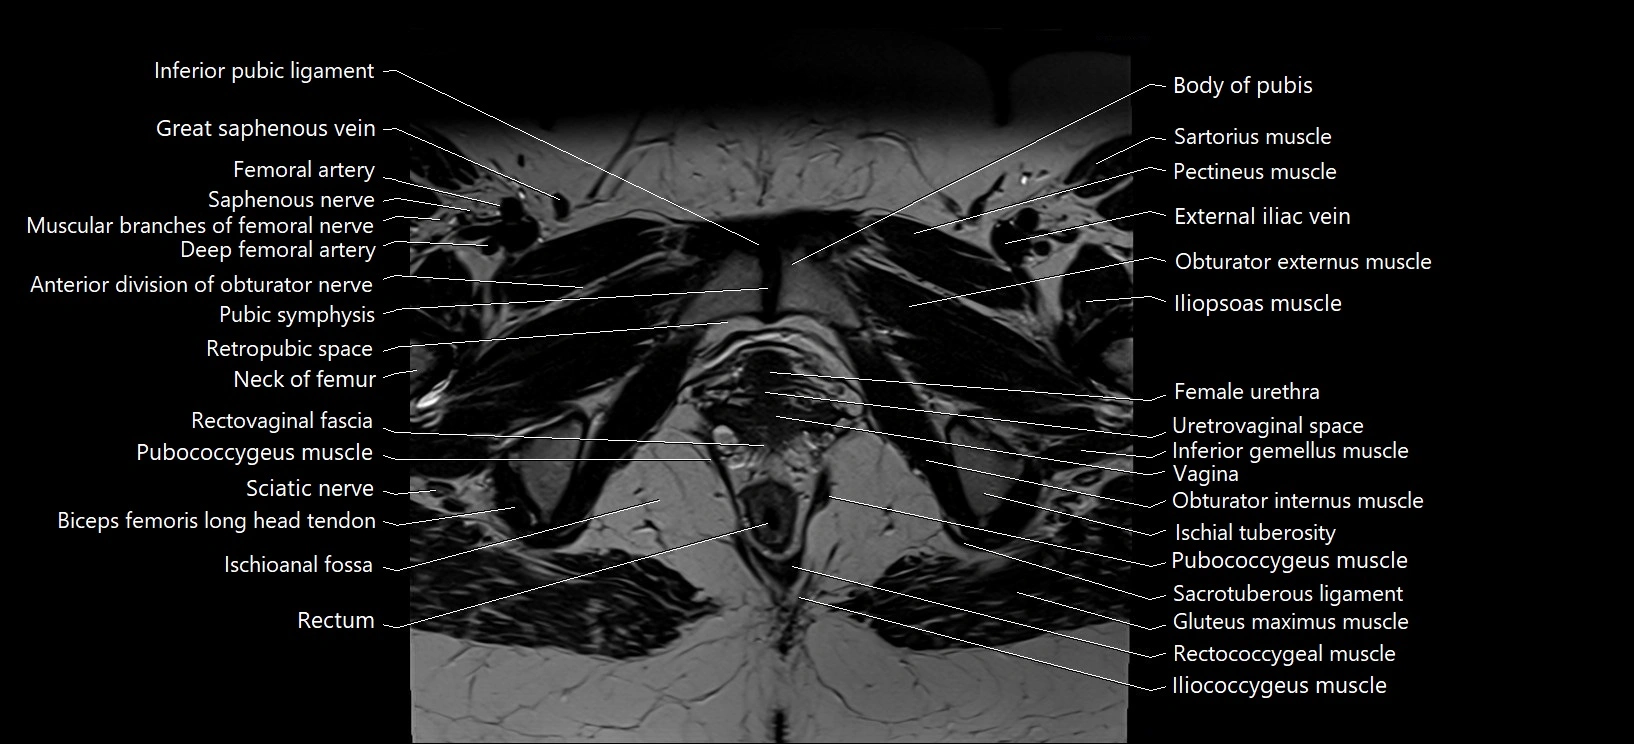

- Anterior division of obturator nerve (Anterior branch of obturator nerve)

- Body of pubis

- Deep femoral artery (profunda femoris)

- External iliac vein

- Femoral artery

- Femoral vein

- Gracilis muscle

- Iliococcygeus muscle

- Iliopsoas muscle

- Iliopubic eminence

- Inferior gemellus muscle

- Inferior pubic ligament

- Ischioanal fossa

- Neck of femur

- Obturator externus muscle

- Obturator internus muscle

- Pectineus muscle

- Pubic symphysis

- Pubococcygeus muscle

- Rectum

- Retropubic space

- Sacrotuberous ligament

- Sartorius muscle

- Sciatic nerve

- Urethrovaginal space

- Urinary bladder

- Vagina

- Vastus intermedius muscle

- Vestibular fossa

- great saphenous vein